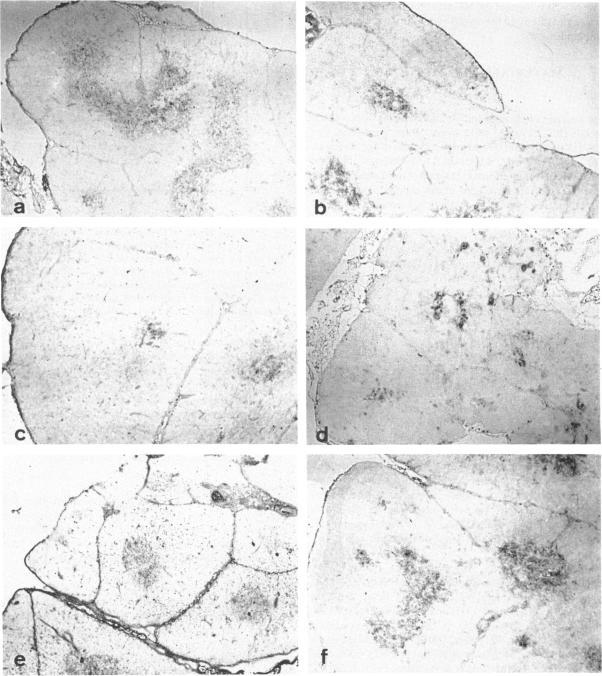

The effect of Cyclosporin A (CyA) administration 20 mg/kg body weight i.p. for 3 or 7 days on rat lymphoid tissues, especially on the thymus, and the recovery after stopping CyA treatment were investigated by both immunoperoxidase technique and flow cytofluorometry using monoclonal antibodies against rat lymphocytes: OX6, OX7, OX8, OX18 and W3/25. The marked reduction of thymic medulla with CyA treatment was clearly demonstrated by staining with OX18. This change was maximal 7 to 10 days after the start of CyA administration. The obvious restitution of the thymic medulla occurred about 7 days after stopping CyA and was almost completed within 14 days. Flow-cytofluorometric analysis of the thymus showed that the percentages of positive cells labelled with OX7, OX8, OX18 and W3/25 appeared to be not changed except for OX18 during and after CyA treatment. However, the expression of each antigen per cell changed in the amount; the peak of fluorescence intensity of OX7+ cells showed a temporary shift to the right during CyA treatment. Bright positive cell populations for each OX8 and W3/25 increased relatively during CyA treatment, and reverted to the normal levels soon after stopping the CyA treatment. On the other hand, bright OX18+ cells decreased with CyA treatment, but this change recovered gradually after stopping the CyA treatment. Treatment with CyA gave no significant changes in the flow-cytofluorometric analyses for these antibodies on lymph node cells. Natural killer cell activity and the ability to cause local graft-versus-host reaction were not inhibited with CyA treatment. These results suggest that CyA inhibits the proliferation and differentiation of thymocytes, or that CyA makes thymocytes migrate rapidly from cortex to periphery.

腹腔注射20mg/kg体重的环孢素A(CyA)3天或7天对大鼠淋巴组织,尤其是胸腺的影响,以及停止CyA治疗后的恢复情况,通过免疫过氧化物酶技术和使用抗大鼠淋巴细胞单克隆抗体(OX6、OX7、OX8、OX18和W3/25)的流式细胞荧光测定法进行了研究。用OX18染色清楚地显示了CyA治疗后胸腺髓质的明显减少。这种变化在开始给予CyA后7至10天最大。停止CyA后约7天胸腺髓质明显恢复,14天内几乎完全恢复。胸腺的流式细胞荧光测定分析表明,除OX18外,在用CyA治疗期间和之后,用OX7、OX8、OX18和W3/25标记的阳性细胞百分比似乎没有变化。然而,每个细胞上每种抗原的表达量发生了变化;OX7+细胞的荧光强度峰值在CyA治疗期间暂时向右移动。在CyA治疗期间,每个OX8和W3/25的明亮阳性细胞群体相对增加,并在停止CyA治疗后很快恢复到正常水平。另一方面,明亮的OX18+细胞在CyA治疗时减少,但在停止CyA治疗后这种变化逐渐恢复。CyA治疗对这些抗体在淋巴结细胞上的流式细胞荧光测定分析没有显著影响。CyA治疗没有抑制自然杀伤细胞活性和引起局部移植物抗宿主反应的能力。这些结果表明,CyA抑制胸腺细胞的增殖和分化,或者CyA使胸腺细胞从皮质快速迁移到外周。